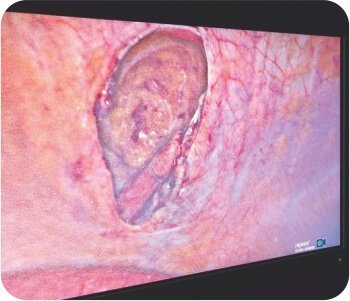

We managed this patient laparoscopically IPOM-Plus with reduction of herniated small bowel, closure of the defect and placing a dual mesh.

Post surgery

Intraperitoneal Onlay Mesh